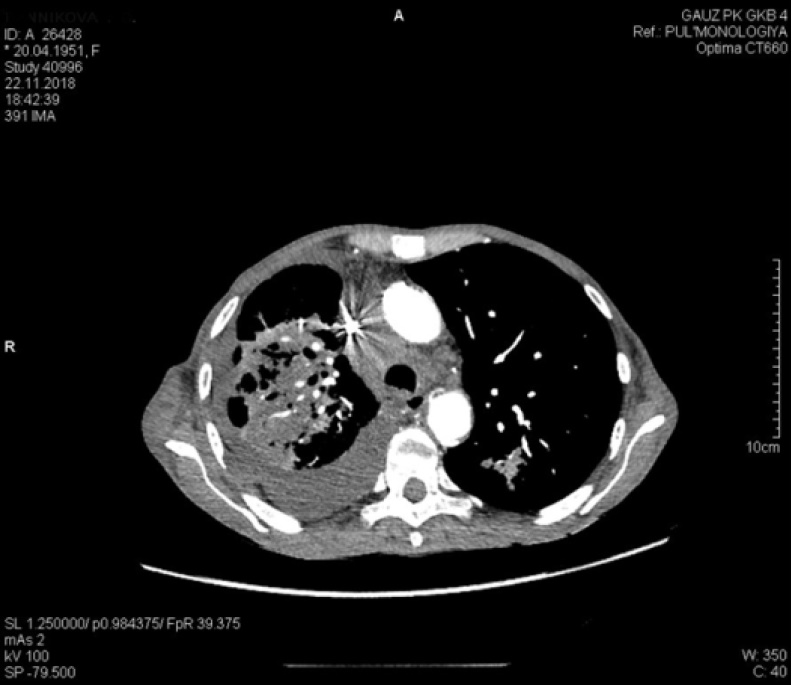

Дообследована с помощью компьютерной томографии органов грудной клетки 18.11.2018 (рис. 4). В плевральной полости справа определяется большое количество жидкости, сепарация листков до 100 мм. Пневматизация правого легкого значительно снижена. В S1-2 левого легкого перисциссурально отмечается появление неправильной формы инфильтрата, с неровными контурами, неоднородного по структуре, размерами до 27 мм. В апикальных отделах S1-2, в S8 левого легкого визуализируются участки локального тяжистого пневмофиброза. Легочной рисунок левого легкого деформирован за счет пневмосклероза, явлений центролобулярной эмфиземы. Определяются многочисленные увеличенные (до 25 мм) внутригрудные лимфоузлы.

Рис. 4. Компьютерная томография органов грудной клетки от 18.11.2018